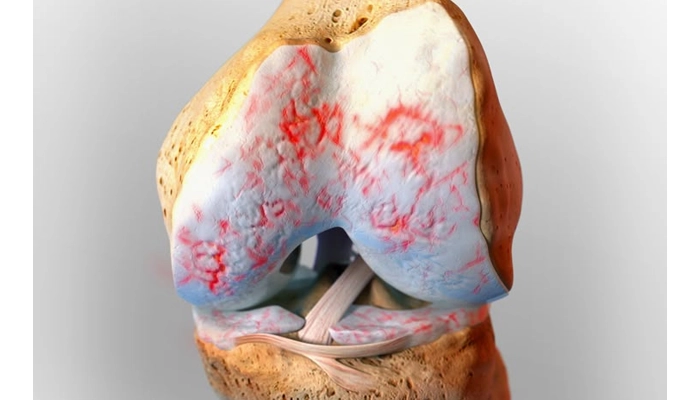

عفونت زانو یکی از جدیترین اختلالات مفصلی است که در صورت عدم درمان بهموقع میتواند منجر به آسیبهای دائمی مفصل، تخریب غضروف و حتی گسترش عفونت به سایر بخشهای بدن شود. این مشکل میتواند به دلایل مختلفی مانند ورود میکروب از طریق خون، آسیبدیدگی یا پس از جراحی در ناحیه زانو بروز کند. شناخت سریع علائم، تشخیص درست و درمان فوری نقش حیاتی در پیشگیری از عوارض جدی دارد.

عفونت زانو زمانی رخ میدهد که باکتری، ویروس یا قارچ وارد فضای مفصلی زانو شود. این حالت با نامهای پزشکی آرتریت سپتیک یا عفونت مفصل زانو شناخته میشود. این عفونت معمولاً با التهاب شدید، درد، تورم و گاهی تب همراه است و نیازمند درمان اورژانسی است.

علائم عفونت زانو

علائم معمولاً سریع و تهاجمی ظاهر میشوند و شامل موارد زیر هستند:

- درد شدید و ناگهانی در زانو

- تورم قابلتوجه مفصل

- گرمی و قرمزی پوست اطراف زانو

عوارض عدم درمان بهموقع عفونت زانو

درمان نکردن بهموقع عفونت زانو میتواند منجر به:

- تخریب دائمی مفصل

- ناتوانی حرکتی و خشکی شدید